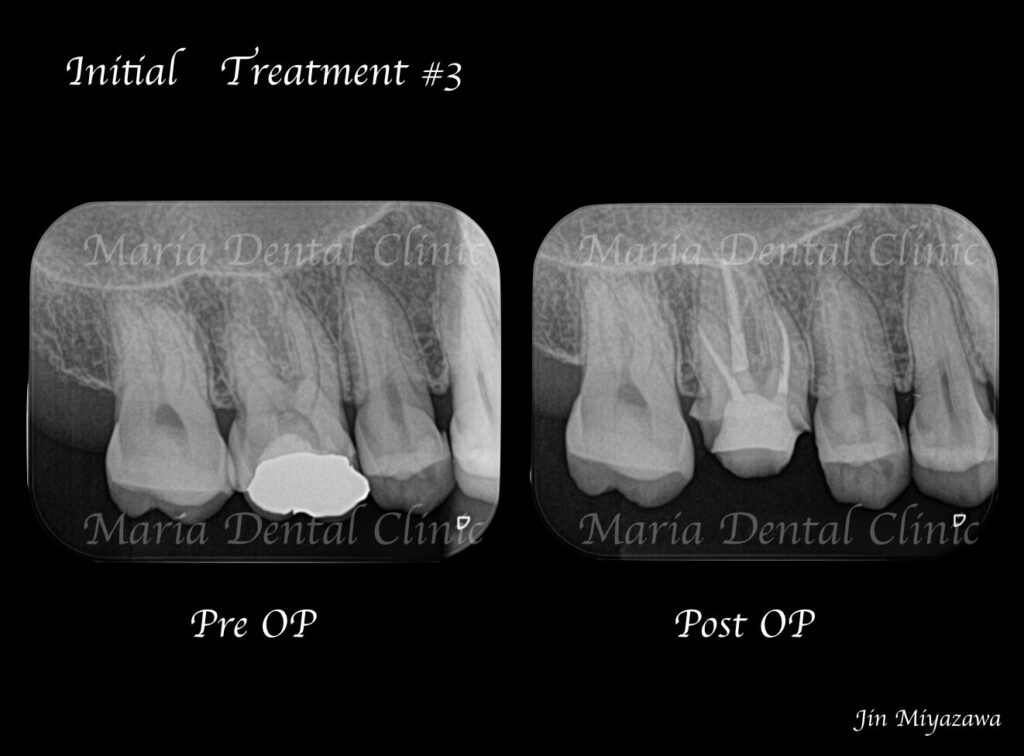

術前の診査より持続性(長い時間)の冷温痛、打診痛を確認し、当院では不可逆性歯髄炎と診断しました。

歯科用拡大鏡、歯科用顕微鏡下にて、軟化象牙質(虫歯)を除去後、歯髄を確認すると一部の歯髄には血流がなく部分壊死を起こしていることがわかる。

今回は術前に歯髄炎による疼痛を確認していたため、水酸化カルシウムを貼薬した後、2回目の治療にて根管充填、支台築造処置を終了させている。

|歯の寿命を左右する初回根管治療_術前術後のレントゲン画像比較-1024x756.jpg)

根管治療において初めての根管治療(抜髄処置)が、その後の歯の寿命を左右する非常に大切な治療になります。 しっかりとコンセプトに沿った根管治療を行うことでより将来的な根尖性歯周炎(骨の中にまで炎症が進行しご自身の歯を残せなくなる場合もあります)になるリスクを最小限に抑えることができます。